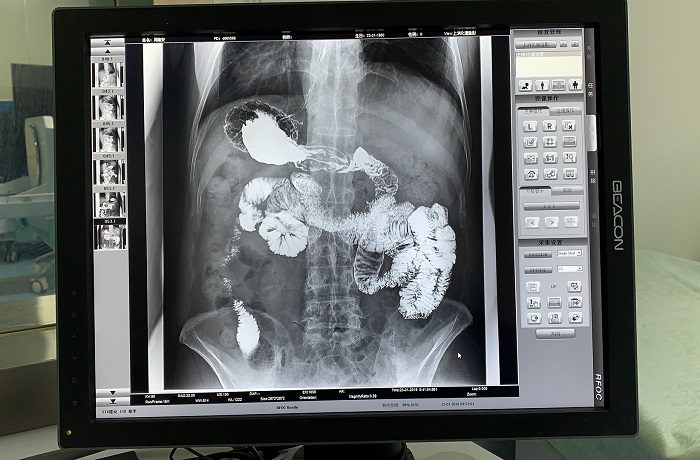

除鋇劑灌腸之外,動態(tài)DRF還適用于胃腸道造影檢查,子宮輸卵管造影等。同時,動態(tài)DRF作為普通數(shù)字X光機使用,滿足全身各部位的數(shù)字化攝影檢查需求;作為具有透視功能的胃腸機使用,滿足全身各部位的數(shù)字化透視、透視下定位、透視下穿刺、透視下點片及簡單的介入治療需求,全面適用于醫(yī)院體檢科、內(nèi)科、外科、骨科、創(chuàng)傷科、急診科等多個科室臨床診斷。

胃腸道造影高清影像